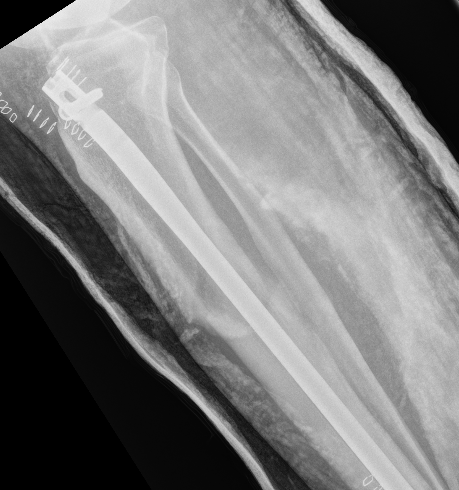

3. Supra-patellar approach with leg semi-extended

- flexed tibia tends to accentuate the deformity

- semi-extended reduces the deformity

- also easier to get lateral and posterior entry point

Smith & Nephew Semi-extended nail

- series of 43 proximal tibial fractures

- treated with suprapatella nail in semi-extended position

- malunion in 4/43 (9%)

- nonunion in 1/43 (2%)